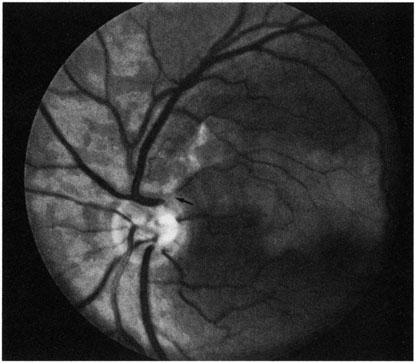

Cilioretinal arteries can be selectively obstructed (Fig. 3). More commonly, however, they occur in association with central retinal vein obstruction.113 When they supply a significant portion of the macula, decreased visual acuity is common. Prognosis for visual outcome in such patients is good. Brown and co-workers114 studied 10 eyes having an isolated cilioretinal artery obstruction. Of those, 60% had an initial visual acuity of 20/40 or better and on follow-up examination, all eyes but one had a best-corrected visual acuity of 20/40 or better.114

Fig. 3. A: Cilioretinal artery obstruction showing opacity of the retina in the area of obstruction. B: The cilioretinal artery has begun to fill after the branches of the central retinal artery but is still not completely filled at this point in the angiogram.